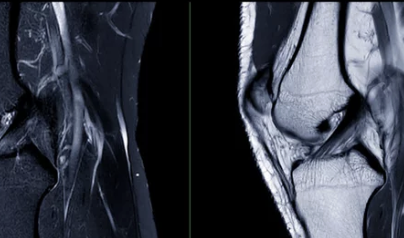

4. 통증 양상으로 구분하는 원인 힌트

무릎에 물이 찰 때 통증의 성격은 원인에 따라 다릅니다.

통증 양상의심 원인

| 욱신거리는 통증 | 관절염 |

| 움직일 때 찌릿함 | 연골·반월상연골 손상 |

| 쉬면 나아짐 | 과사용 |

| 밤에도 아픔 | 염증 지속 |

5. 무릎에 물이 차는 대표적인 원인

무릎에 물이 차는 이유는 하나가 아닙니다.

흔한 원인들

- 퇴행성 관절염

- 반월상연골판 손상

- 인대 손상